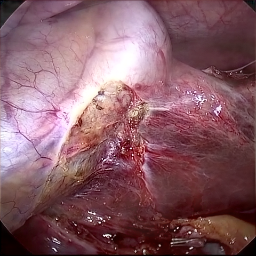

Refer to caption (a) Input Refer to caption (b) case1 Refer to caption (c) case2 Refer to caption (d) case3 Refer to caption (e) Ours Refer to caption (f) Target

Figure 4: Ablation comparisons sampled from the DesmokeData and LSD3K datasets. The first two rows are from DesmokeData and the last two rows are from LSD3K. (settings: case1 = ADA+CrossGating, case2 = DHA+CrossGating, case3 = DHA+ADA).

IV-D Ablation Studies

To validate the effectiveness and individual contributions of the core components of our proposed RGA-Net, we conducted a series of ablation experiments on the DesmokeData dataset. We systematically analyzed the impact of our key designs: the DHA module, the ADA module, and the Cross-Gating (CG) mechanism for feature fusion. In these studies, we created several variants of our network by removing or replacing one component at a time and evaluated their performance. The quantitative results of these experiments are presented in Table II, and qualitative visual comparisons are shown in Fig. 4.

IV-D1 Effectiveness of the Dual-Stream Hybrid Attention Module

The DHA module is designed to capture both local surgical details and global illumination changes by combining shifted window attention with a frequency-domain processing branch. To ablate its effect, we replaced the DHA modules in the encoder with standard Swin Transformer blocks, thus removing the spectral pathway and the hybrid attention mechanism. As demonstrated in Table II, this variant experienced a significant drop in performance. This decline highlights the importance of integrating frequency-domain information, which is crucial for handling the complex light scattering caused by surgical smoke and restoring high-frequency textural details. The results confirm that the dual-stream approach provides a richer feature representation than spatial attention alone.

IV-D2 Effectiveness of the Axis-Decomposed Attention Module

We then investigated the contribution of the ADA module, which is employed in the decoder and latent space to efficiently process multi-scale features. We created a variant where the ADA modules were substituted with a more conventional self-attention mechanism without the block and grid axis decomposition. The results in Table II show a clear degradation in performance for this variant compared to the full model. This outcome validates that factorizing attention along two distinct axes allows the model to capture both fine-grained local patterns and long-range spatial dependencies more effectively and efficiently. The ADA module’s design provides a powerful yet computationally manageable way to model complex feature relationships during the reconstruction phase.

IV-D3 Effectiveness of the Cross-Gating Mechanism

Finally, we analyzed the efficacy of the cross-gating mechanism used for multi-scale feature fusion between the encoder and decoder. We replaced our CG blocks with a standard skip-connection method, specifically simple concatenation followed by a convolutional layer, as is common in many U-Net-based architectures. As shown in Table II, this change resulted in a substantial performance decrease. This finding underscores the superiority of the bidirectional feature modulation offered by our CG mechanism. Unlike simple fusion, cross-gating allows the encoder and decoder pathways to selectively amplify relevant features and suppress irrelevant information from each other, leading to a more refined and effective integration of multi-scale context, which is vital for high-quality image reconstruction.

In conclusion, the ablation studies comprehensively demonstrate that each of our proposed components—DHA, ADA, and CG—is integral to the overall performance of RGA-Net. The full model consistently outperforms all ablated variants, proving the synergistic benefits of our architectural design for the challenging task of surgical smoke removal.